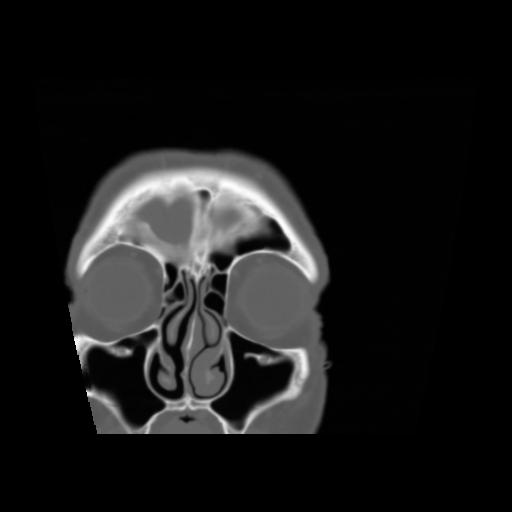

5 CEREBRO,,Coronal,3.000,CEREBRO,Coronal,